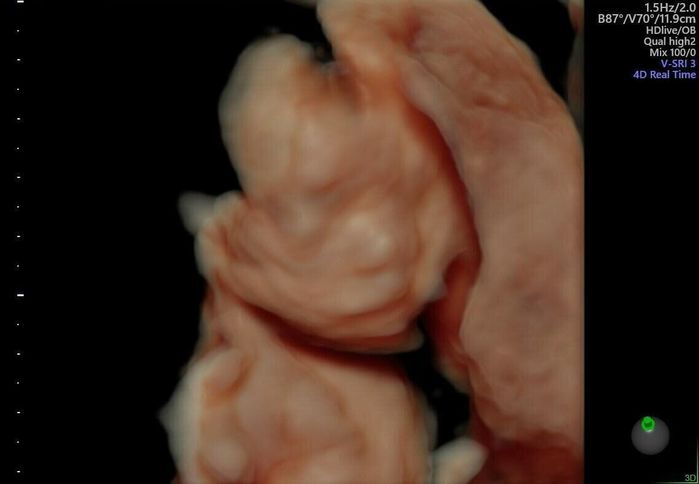

3634g、55.0cmのBIGboy誕生しました!